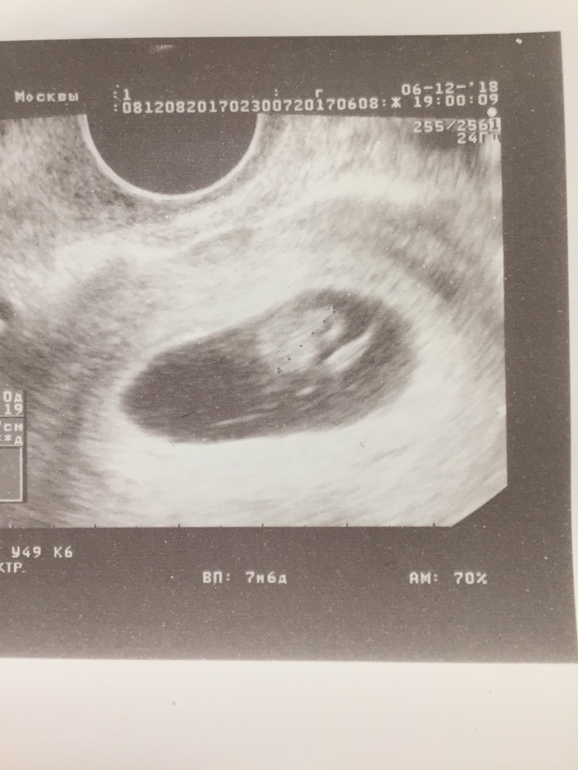

УЗИ 7 недель 6 дней

Итак, 7 недель 6 дней:

- Сердцебиение 160 ударов в минуту

- Длина 1 см